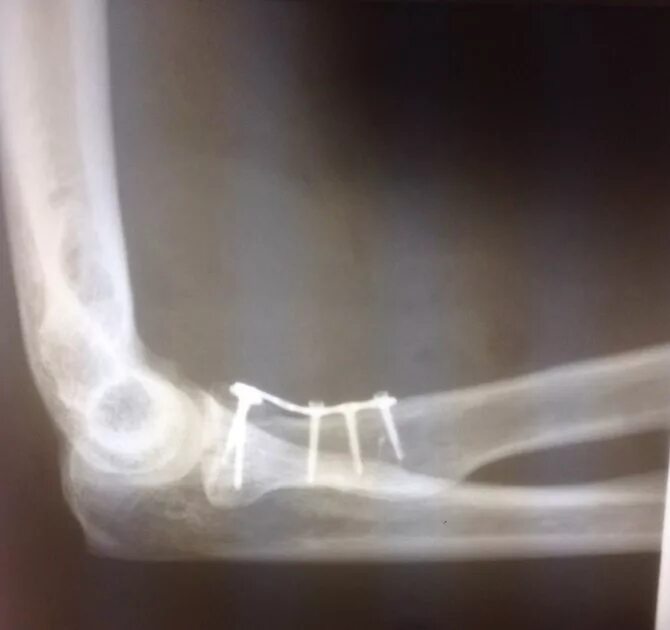

Закрытый перелом предплечья код по мкб 10